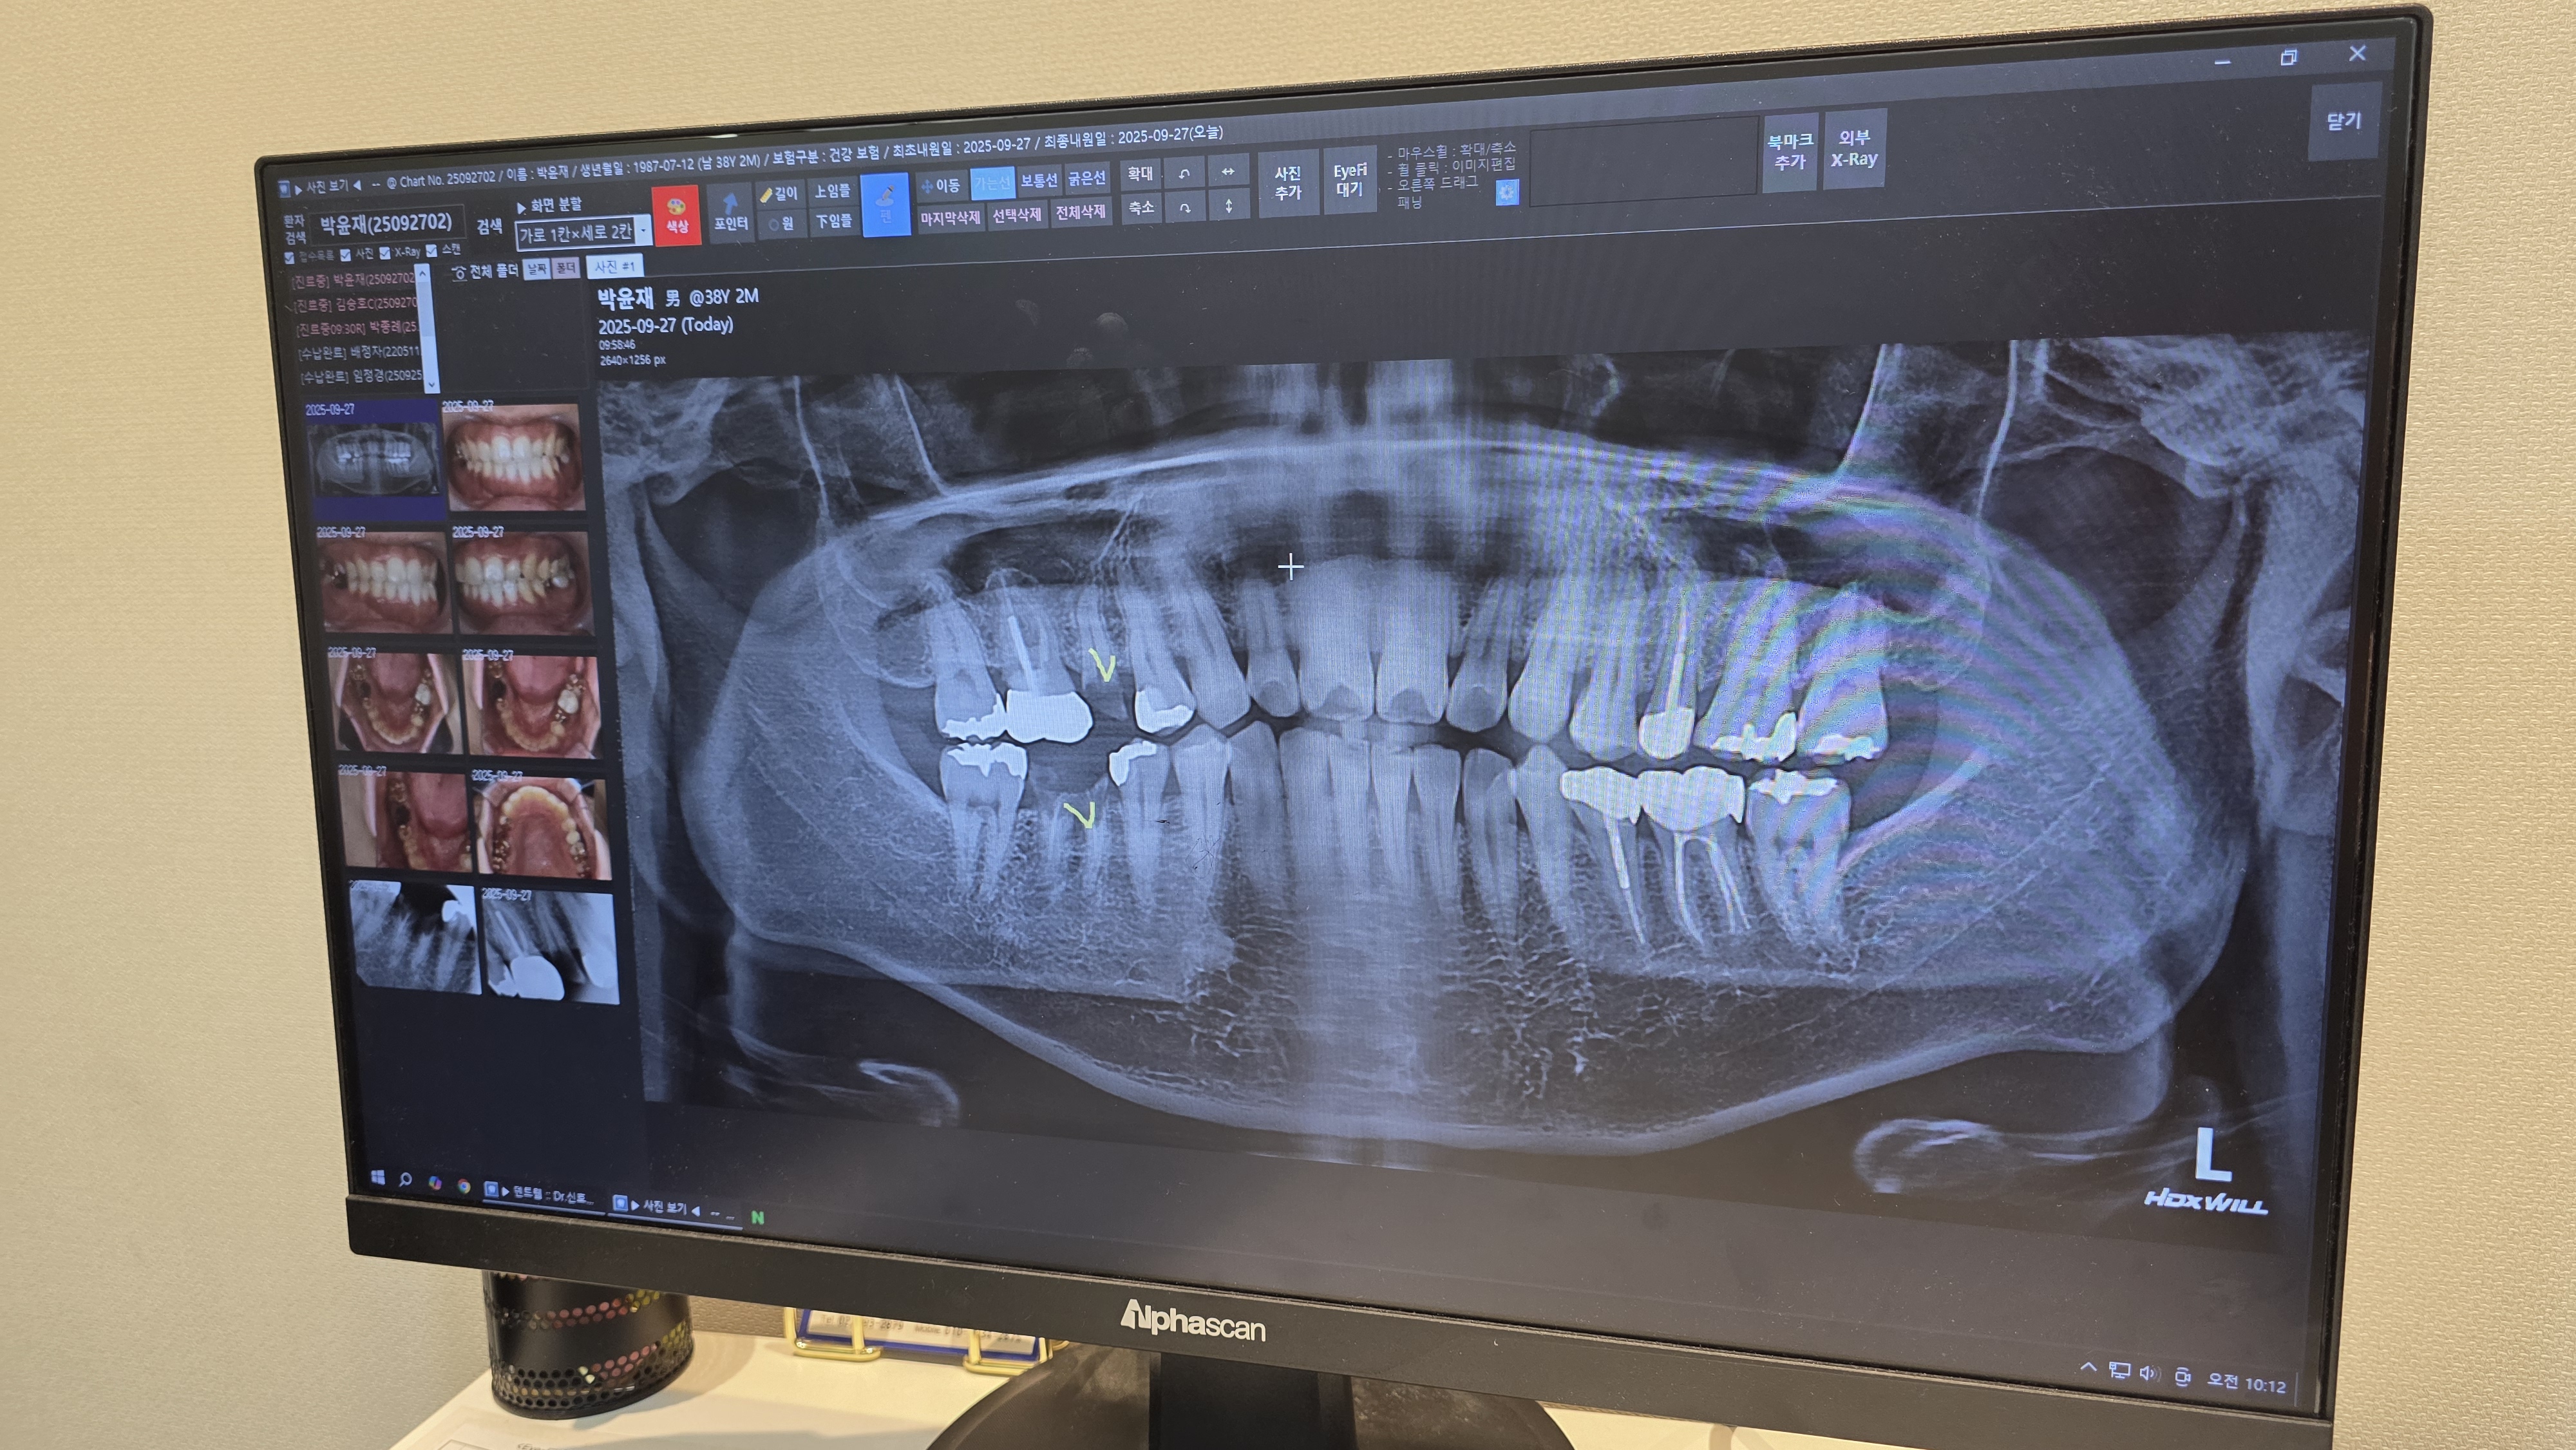

- 09:40 더바른치과 방문, 엑스레이 촬영 및 상담 → 어금니 발치 및 뼈 이식(456,000원)

- 윗 어금니는 뿌리 휘어져 있어 시간이 오래 걸림

- 아랫 어금니는 뿌리까지 썩어 있어 통증 동반 → 마취 추가하며 발치

- 엑스레이 사진